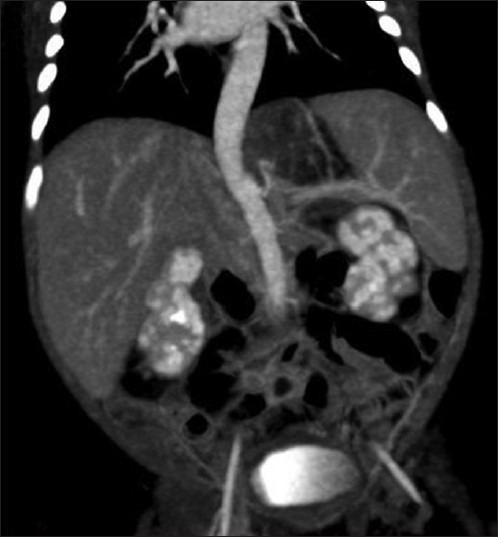

膈下叶外型肺隔离症:伪装成肾上腺肿块。

Infradiaphragmatic extralobar pulmonary sequestration: masquerading as suprarenal mass.

Pulmonary sequestration is a rare malformation, wherein a portion of lung is non-functional and is not in normal continuity with the tracheo-bronchial tree, and may derive its blood supply from systemic vessels. Two types are described: Intralobar and extralobar types. Intralobar sequestration is more common type, which shares visceral pleura of the involved lobe and is localized within the normal pulmonary parenchyma. Whereas extralobar forms are uncommon and are totally separate from the lung and usually have own covering. Infra-diaphragmatic pulmonary sequestration is of extralobar type and is extremely rare, and usually is associated with other congenital malformations. We present an extremely rare case of isolated infra-diaphragmatic pulmonary sequestration which was antenatally detected and followed up with postnatal CT scan, where it masqueraded as suprarenal mass, and was surgically treated. This case emphasises to add a differential diagnosis of malformation in congenital supra-renal masses, which remain stable in size and appearance, and hence avoid immediate surgery.

摘要

肺隔离症是一种罕见的畸形,其中一部分肺组织无功能,与气管支气管树无正常连续性,且其血液供应可能来自体循环血管。可分为两种类型:叶内型和叶外型。叶内型肺隔离症较为常见,与受累肺叶的脏层胸膜相连,位于正常肺实质内。而叶外型较少见,与肺完全分离,通常有自己的被膜。膈下肺隔离症属于叶外型,极为罕见,通常与其他先天性畸形相关。我们报告了一例极其罕见的孤立性膈下肺隔离症病例,该病例在产前被检测到,并在出生后进行CT扫描随访,其在CT上表现为肾上腺肿块,最终接受了手术治疗。该病例强调在先天性肾上腺肿块的鉴别诊断中应增加对畸形的考虑,这类肿块在大小和外观上保持稳定,因此应避免立即手术。